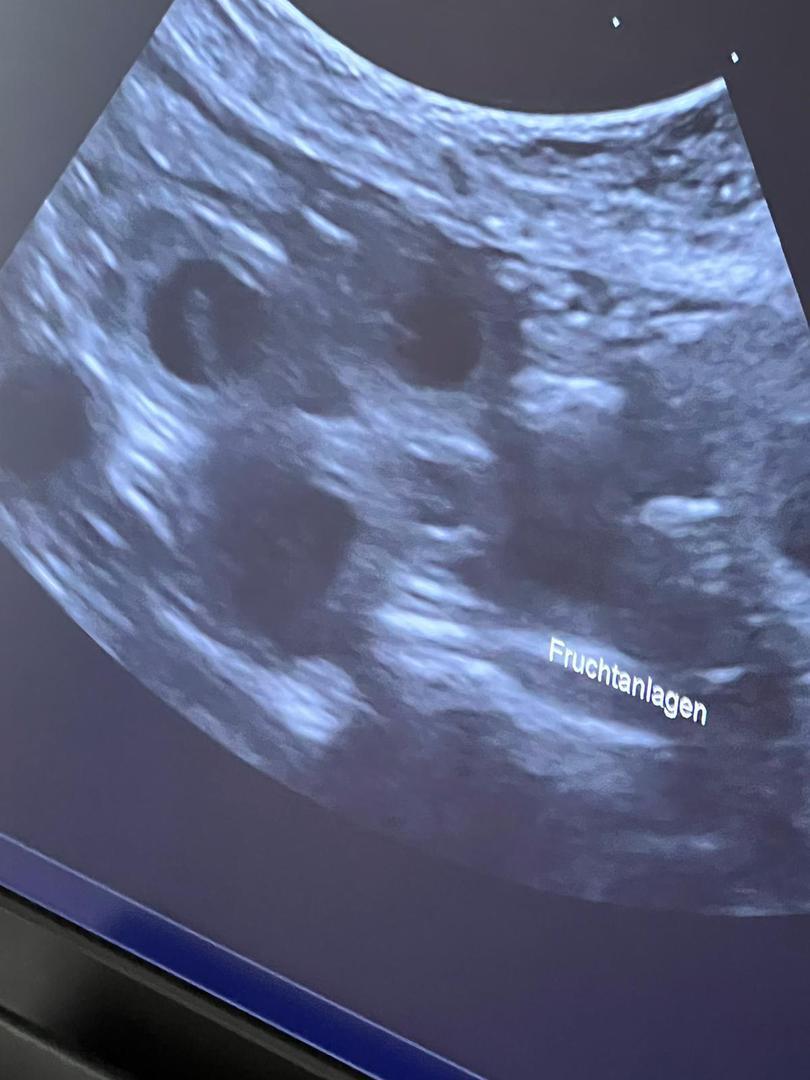

Am 12.08.2022 konnten wir mittels Ultraschall die Trächtigkeit bestätigen.